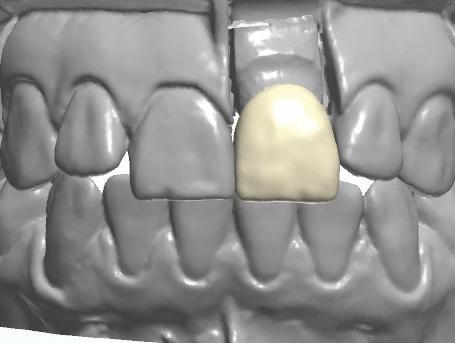

Figure 4. Maxillofacial surgery. Figure 6. TMJ analysis. Figure 8. Airway analysis. Figure 10. Periodontics. Figure 5. Orthodontics. Figure 7. Implant placement. Figure 9. Prosthodontics. Figure 11. Endodontics.